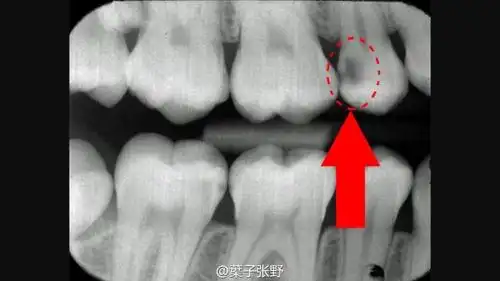

看看看看,暗影部位,蛀牙已经很深了.